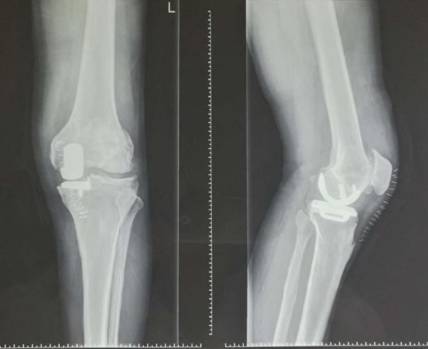

全膝表面置换术治疗重度骨关节病

优点:疗效可靠,膝关节病的最终解决方案。

术前术后对比

全膝关节翻修术